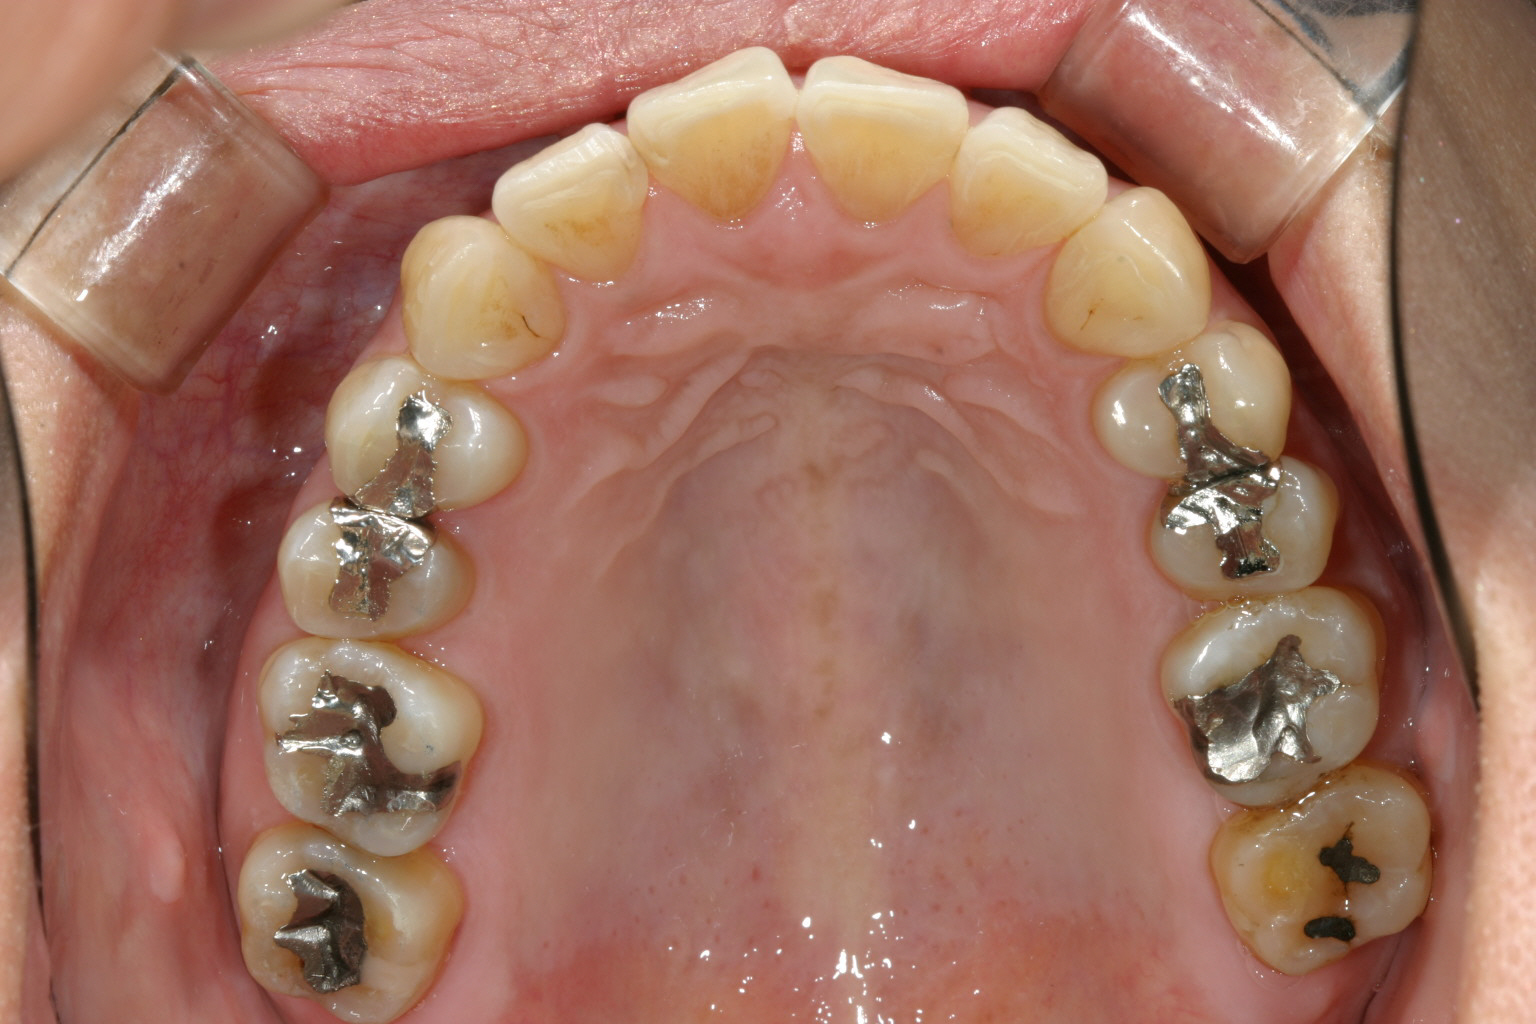

上顎にはさほど乱れを認められません。

左右の臼歯部に高さの誤った冠が被っている為、後にこれを8本入れ替え正常な顎位に変更する。

上顎にマルチループワイヤーを入れアーチフォームを改善する。 アーチフォームもU字変更している。